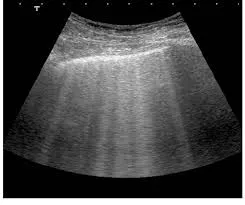

Vazamento com desenvolvimento de edema da parede abdominal.